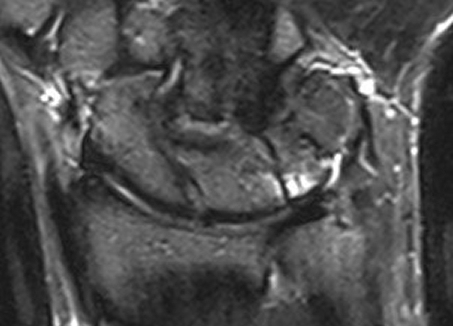

Magnetic Resonance Imaging showed a bone marrow edema adjacent to the fibro-cartilage coalition as well as hyaline cartilage in the distal notch (Figure 3 [Fig. 3], Figure 4 [Fig. 4]).

Figure 4: Magnetic Resonance Imaging of the right wrist in the cartilage-sensitive DESS (Double echo steady state) sequence showing hyaline cartilage in the distal notch and fibro-cartilage tissue proximally without cartilaginous coating as typical for luno-triquetral coalition type II of Minaar’s Classification